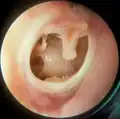

The oval perforation in this left tympanic membrane was the result of a slap on the ear

A subtotal perforation of the right tympanic membrane resulting from a previous severe otitis media